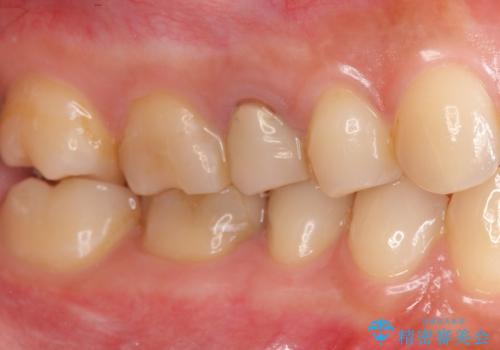

患者様の天然歯はグラデーションがあり切縁(歯冠の先端)はやや透けていて透明感があるのに対し、前歯(右上1)の差し歯はやや黄色く不透明で単調な色味でした。

患者様のご希望により、右上1はジルコニアクラウン(スペシャル)、右上5はジルコニアクラウン(スタンダード)へやりかえることにしました。

前歯のクラウンは一度修正し、患者様の理想とする色味や形態を追求しました。

天然歯と見紛うほどの自然な仕上がりに喜んで頂けました。

ジルコニアクラウンの繊細なグラデーション・透明感は熟練した技工士さんの技術の賜物です。